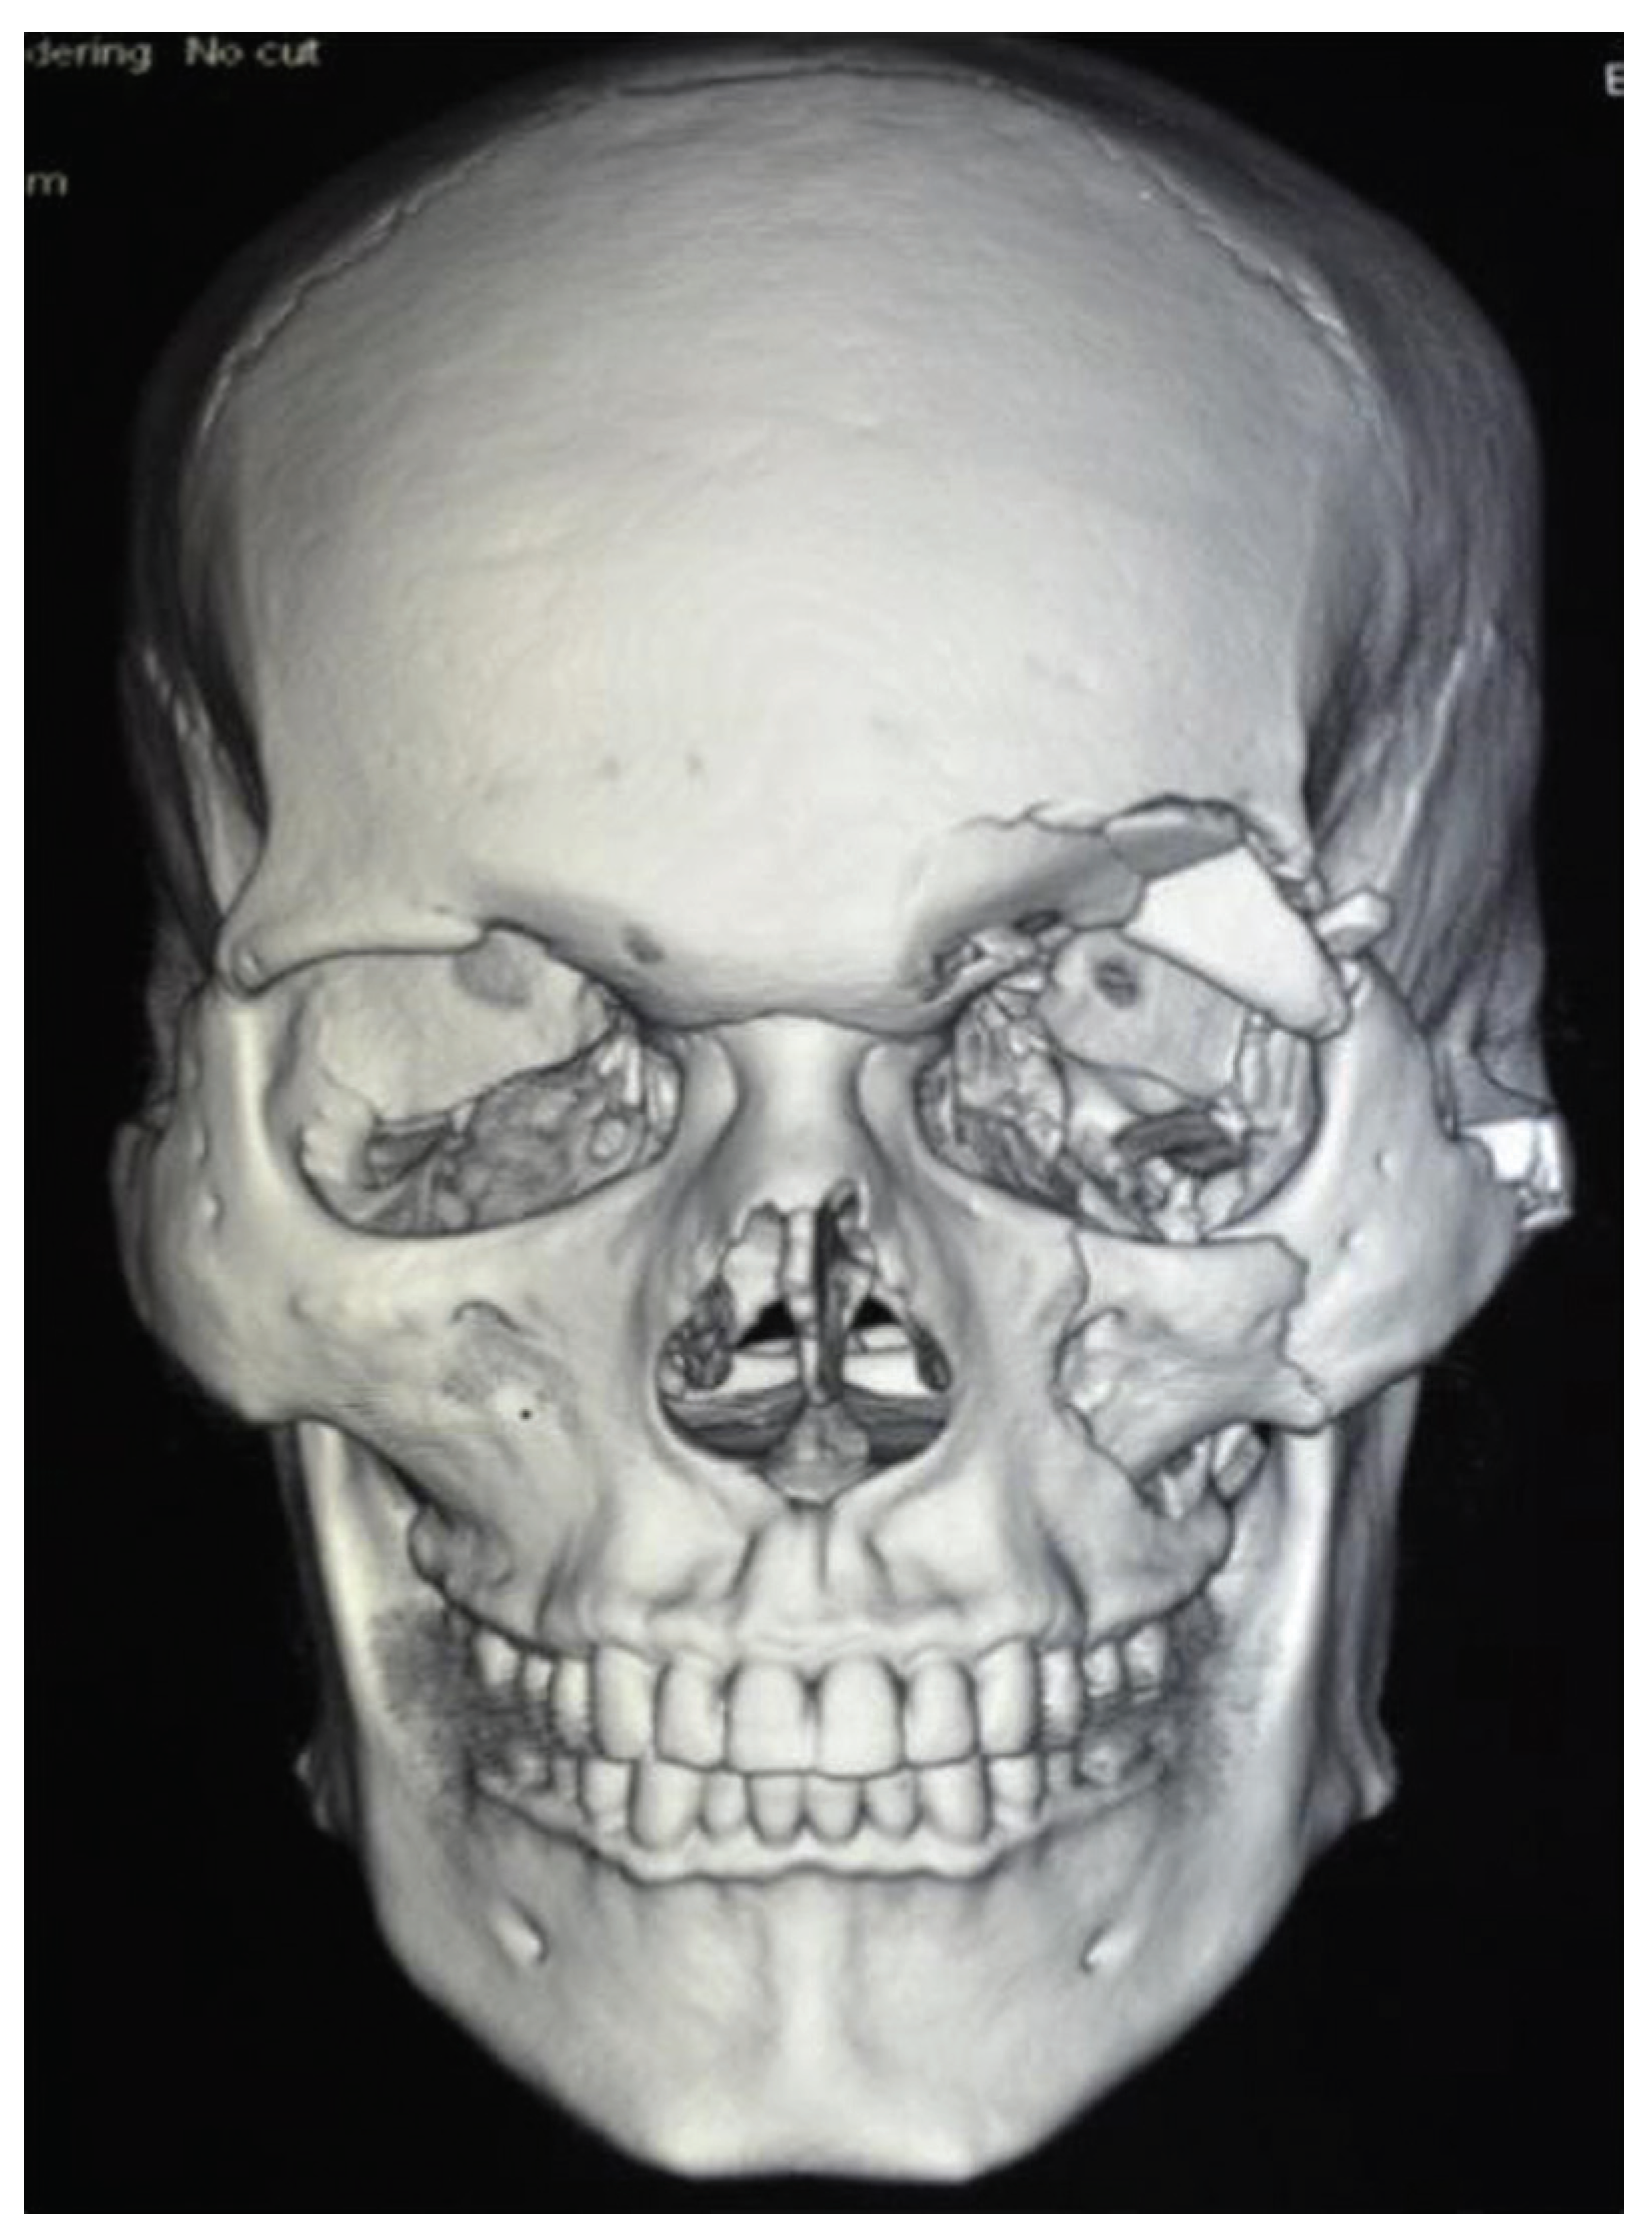

Figure 1.

Mapping the orbital content with marker in continuous axial, sagittal, coronal sections.

Figure 2.

Using CT-VCT 64 slice XT console, preand postoperative CT [12] scans were done for the patients with 120 kV, 250 mA, and slice thickness with appreciation of 2 mm. Retro reconstruction was done at 0.625 mm in a bone window of window width 2,000 and window length 350: soft-tissue window of window width 300 to 350 and window length 100 in an advance workstation ADW 4.4. The anterior border of the orbital floor was determined using first CT slice and the posterior border is the apex of orbital cavity. Orbital volume [13] is measured in axial, sagittal, and coronal sections (Figure 1 and Figure 2) by selecting mapping tool provided with the software of computer program, and orbital volume within the bony borders is mapped in every slice to calculate the orbital volume automatically displayed on the monitor (Figure 3, Figure 4 and Figure 5) after the end of mapping.

Figure 6.

Pre-operative CT-PNS image of a patient.